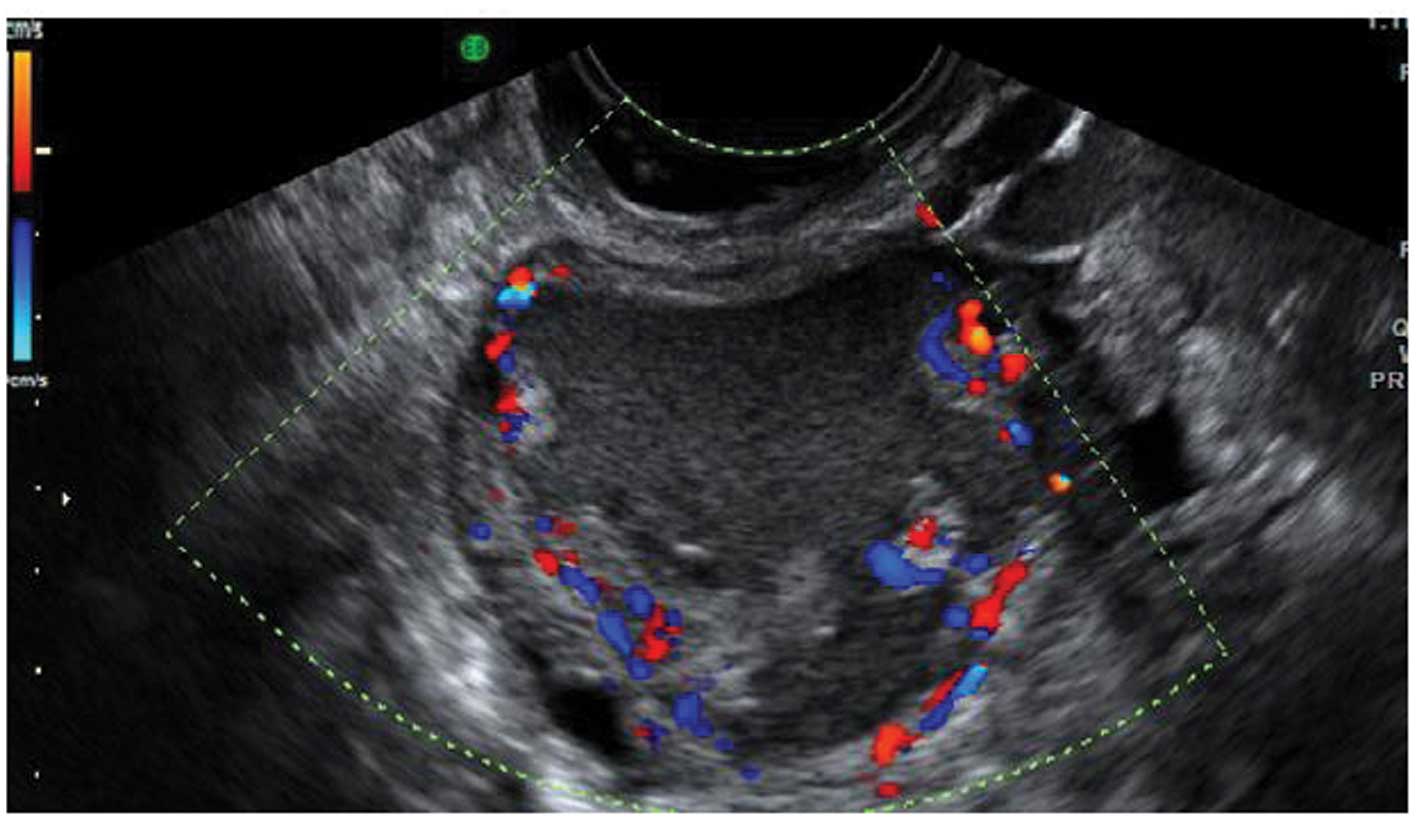

Endometriomas may also have atypical features, and frequently debris within the cyst may give the impression that it is a unilocular-solid lesion with solid papillary projections. In postmenopausal women the appearances of an atypical endometrioma should be examined very carefully as there is a significant risk of malignancy in such lesions in this age group (29,32) (Fig. 16).

Figure 16

Atypical endometriomas with solid papillary projections. (A) Multilocular solid endometrioma. (B) Unilocular solid endometrioma.

During pregnancy endometriomas can change their appearance secondary to decidualization. The features may become quite alarming, with solid vascular projections into the cyst cavity. When no pre-existing scan of the ovary is documented it is difficult in these cases not to suspect malignancy (Fig. 17), although papillary projections were a more frequent sonographic feature among malignant lesions than among benign endometrioid cysts (34,35).

Figure 17

Decidualized endometrioma in pregnancy with vascularized papillary projections.